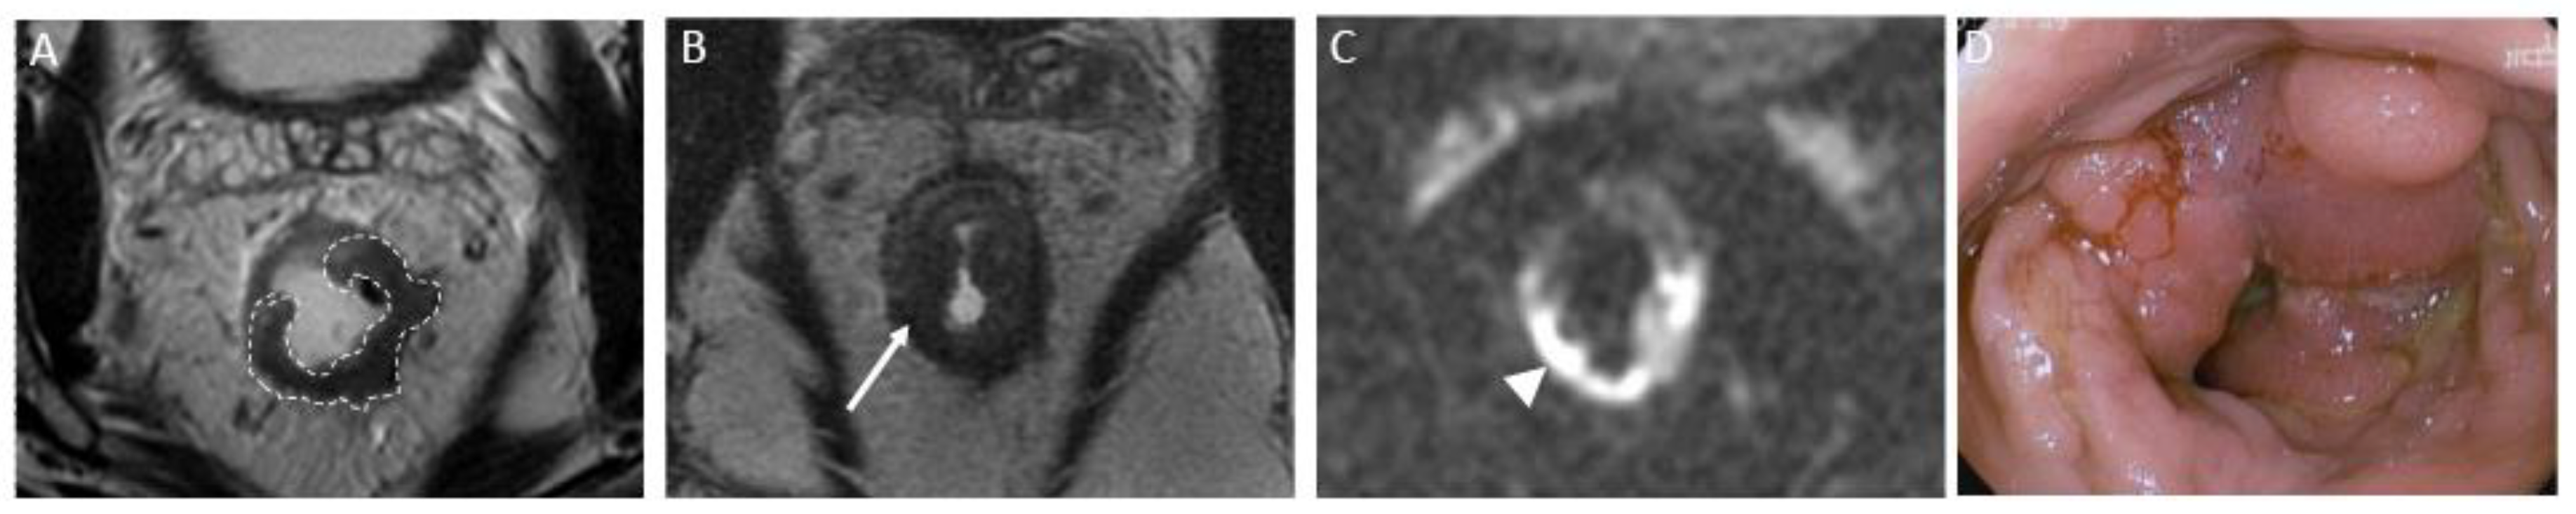

a) CR signifies the remarkable disappearance of T2 intermediate signal, indicating a significant reduction in tumor size and suggesting a highly favorable response to treatment. T2WI and DWI changes are described below and exemplified on Figure 2:

T2-Weighted Imaging – On T2WI, complete response can be represented as a linear or crescent-shaped scar within the mucosal/ submucosal layers, or even the normalization of the rectal wall. It is known that rectal wall normalization can be seen in 5% of cases and is suggestive of complete response (55).

Diffusion-Weighted Imaging – Complete response on DWI is characterized by the absence of high signal intensity on high b-value DWI images (56-59). It is essential to compare with the baseline and use the normal rectum as references. This criterion can be especially valuable in identifying complete response in small, subcircumferential scars (60).

Figure 2. Complete response after neoadjuvant chemotherapy in a 54-year-old man with low rectal adenocarcinoma. (A) Baseline axial T2-weighted MR image shows a low rectal tumor (dotted line). (B) Axial T2-weighted MR image after completion of neoadjuvant chemoradiotherapy shows a thick hypointense scar at the site of the treated tumor (arrow). No diffusion restriction was present on diffusion-weighted images (C), and no residual malignancy was identified at endoscopy (D). The patient was offered a watch-and-wait strategy and has been without evidence of disease for 36 months.